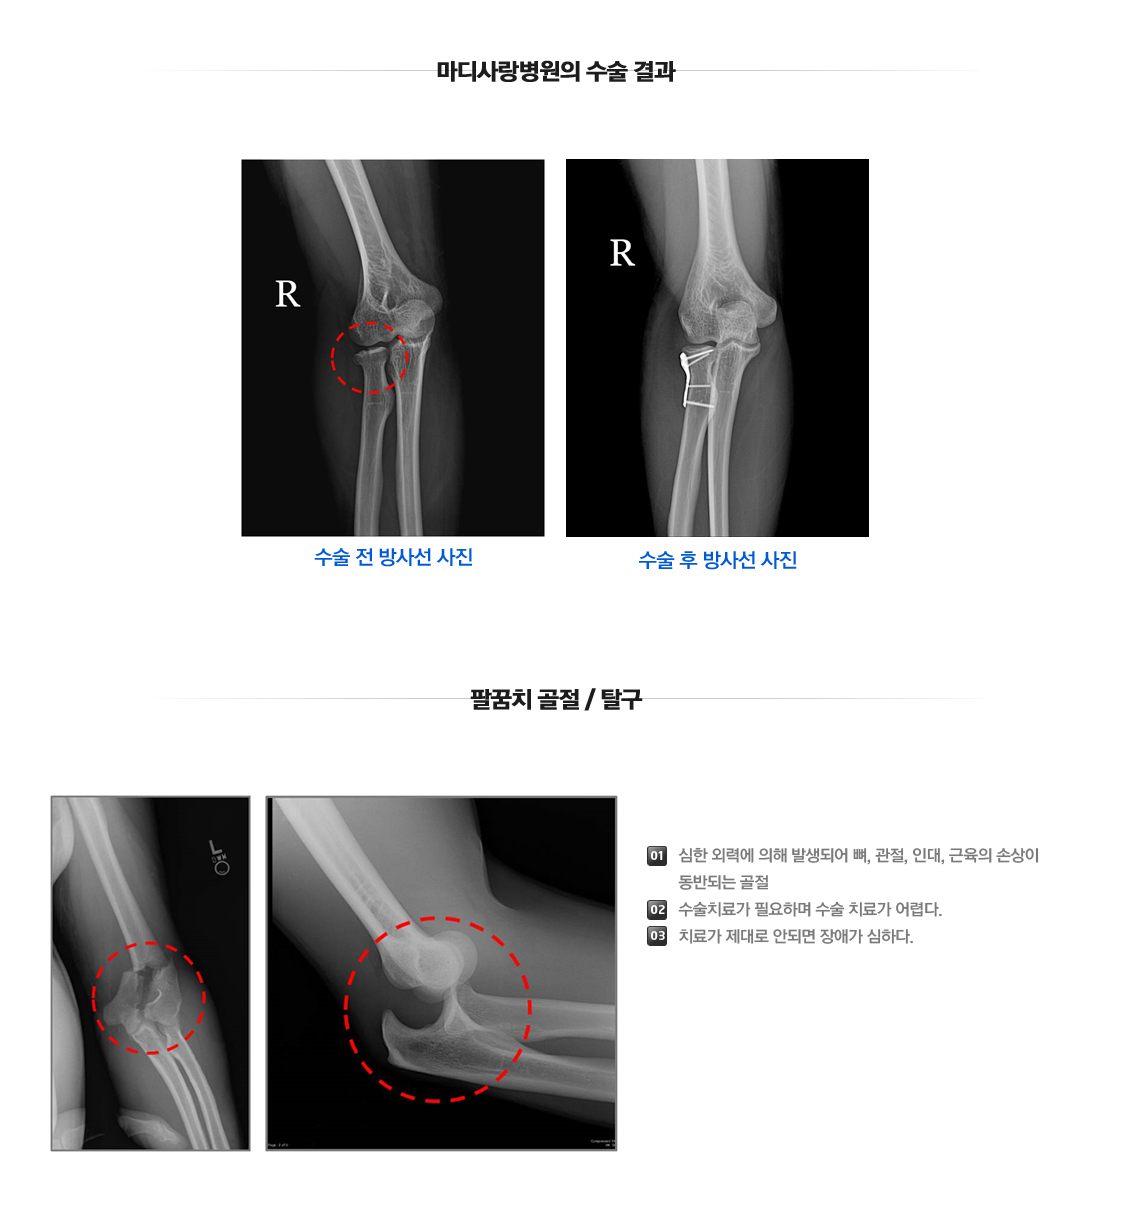

관절주위골절(팔꿈치)

팔꿈치 골절수술

Fracture